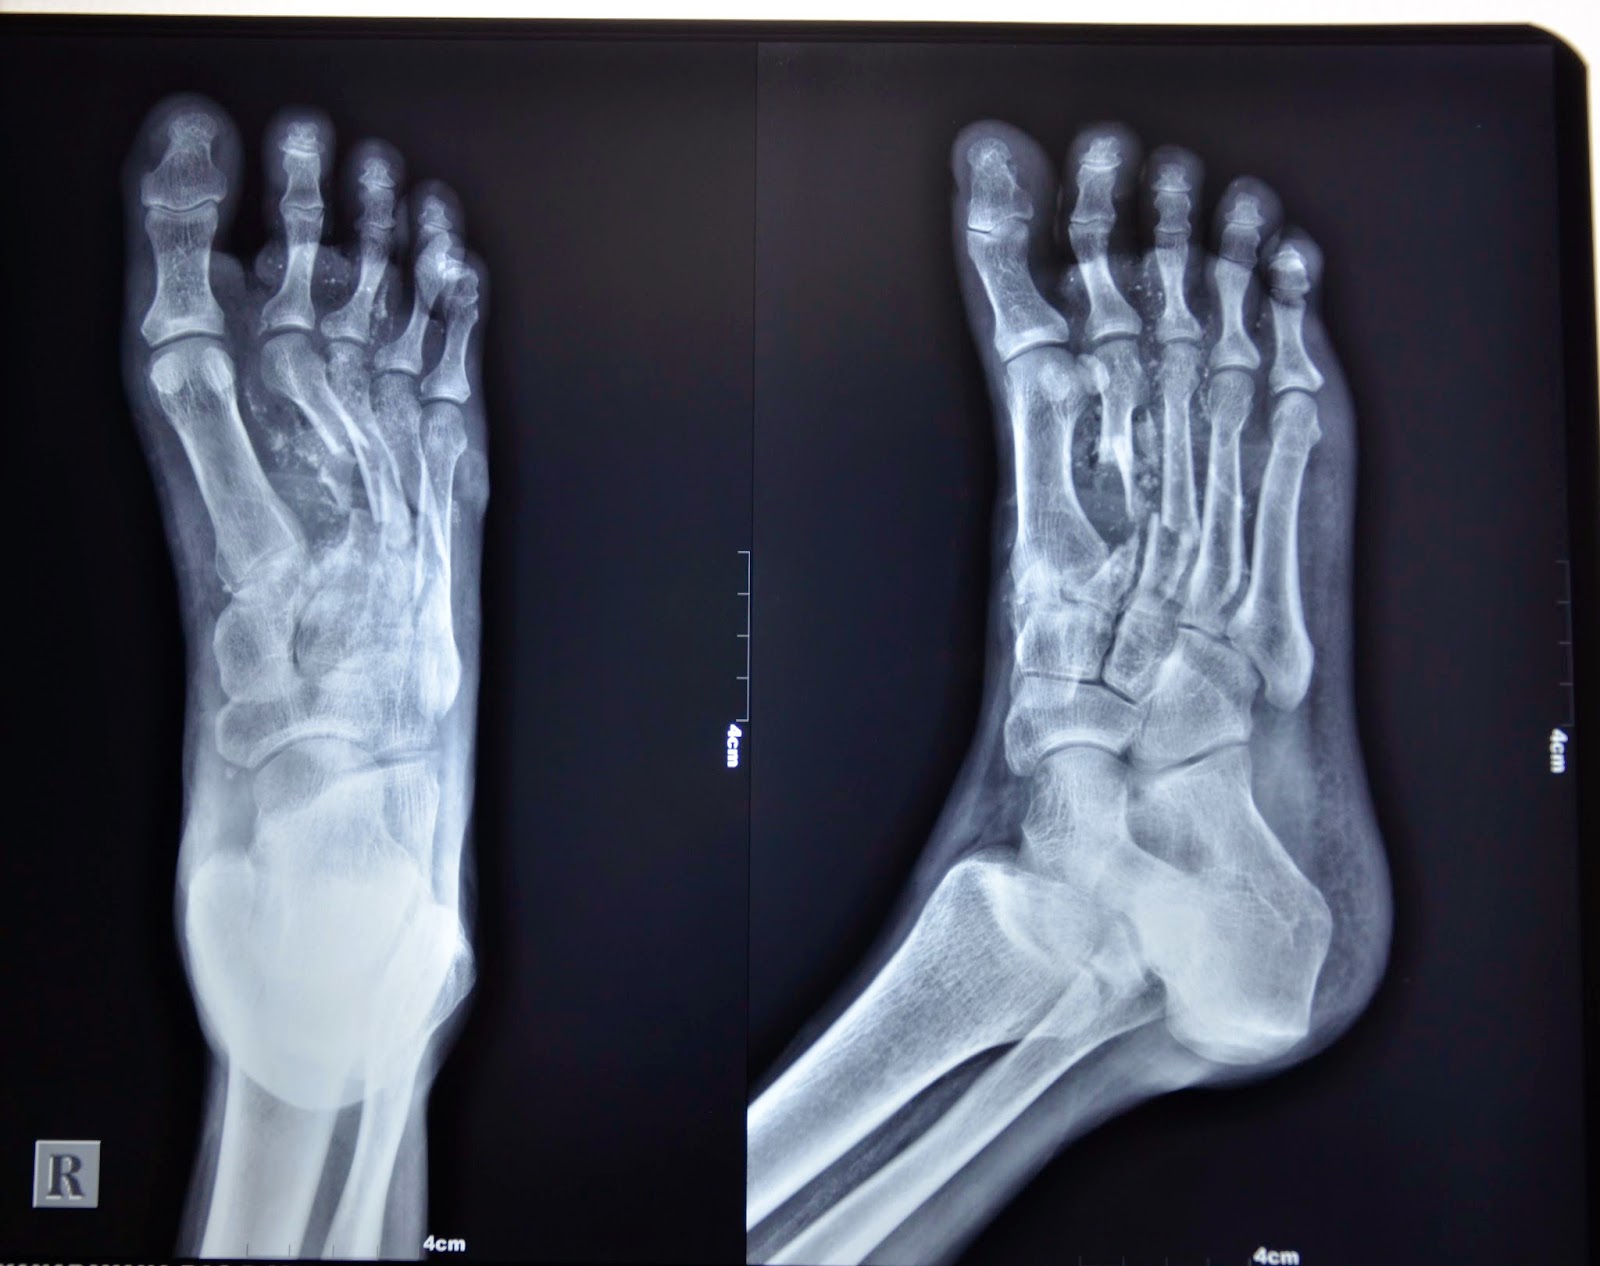

Stress Fracture On X Ray Crush Fracture In Foot This can subsequently cause extensive soft tissue (i.e. direct causes are traumas that crush the lisfranc joint, like car accidents or something falling on your foot at a. fractures can result from a direct blow to the foot — such as accidentally kicking something hard or dropping a heavy object. These wounds are usually very serious, involving. This. Crush Fracture In Foot.

Radiographie d'un pied montrant une fracture dans la phalange Crush Fracture In Foot You can also break a bone through overuse or repetitive stress. clinical details are paramount in foot radiography, injuries to the 5th tend to be from inversion type injuries whilst the. This common injury requires prompt medical attention and can be serious. foot crush injuries are more severe than regular foot fractures. a broken foot, or foot. Crush Fracture In Foot.